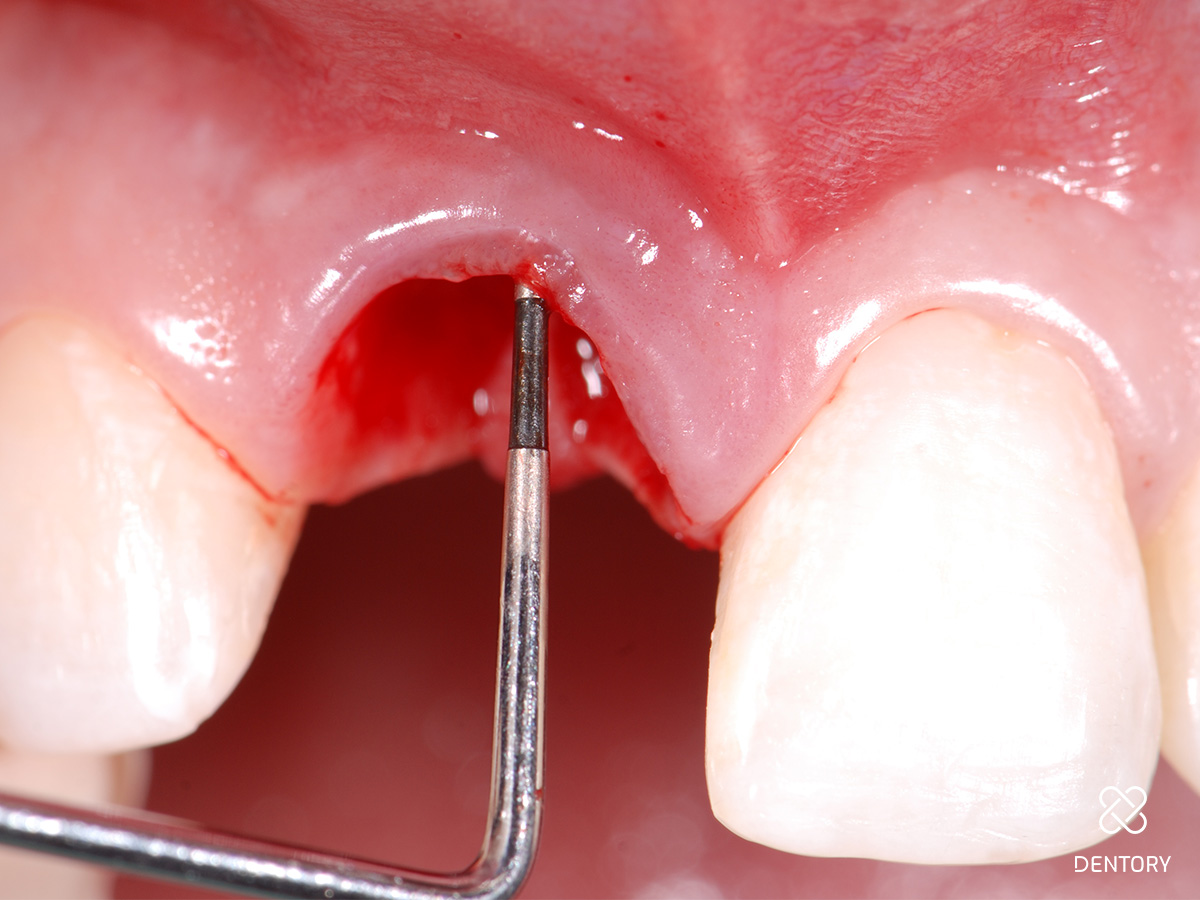

Abbildung 5

Sondieren der bukkalen Knochenstrukturen mittels Biotyp-Sonde; im Bereich der Resorption kam es zum lokalen Verlust der vestibulären Lamelle.